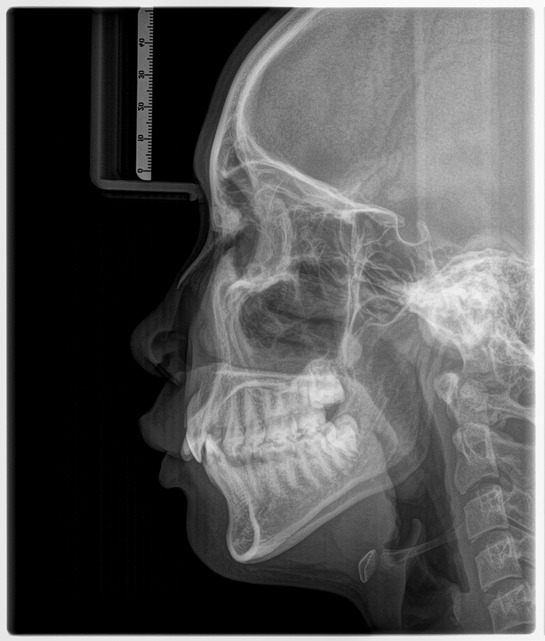

4. 세팔로 엑스레이

①두개골 측면을 촬영

②용도

●교정 치료 계획 수립

●턱 위치/비대칭 분석